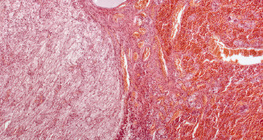

zumiranje: 50x